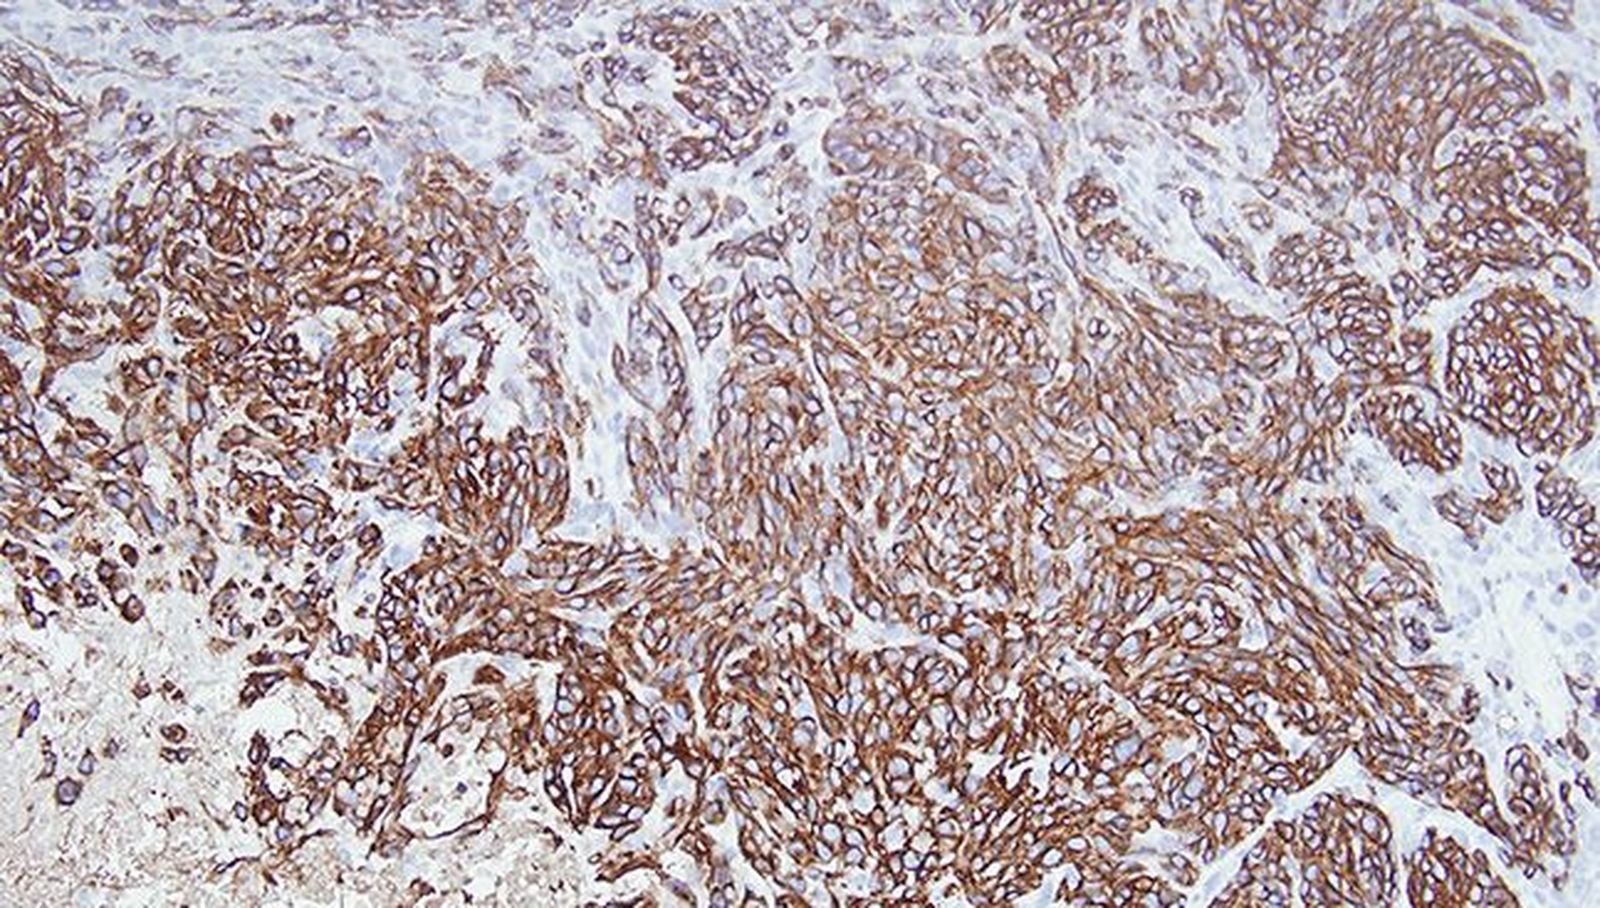

El grupo dirigido por David Santamaría en, el Centro de Investigación del Cáncer (Universidad de Salamanca-CSIC), contribuyó a la investigación original liderada por científicos de Revolution Medicines, en colaboración con investigadores de EE.UU. y Europa, dando como resultado la caracterización preclínica de un novedoso inhibidor del estado activo de RAS (RAS(ON)). El trabajo el 8 de abril en Nature, describe RMC-7977, un compuesto preclínico con un perfil inhibidor multiselectivo de RAS(ON), que fue diseñado para inhibir el espectro completo de mutaciones oncogénicas de RAS, incluyendo mutaciones del codón 12 de RAS (RAS G12X) así como las formas de RAS no mutadas. El RMC-7977 se une a la chaperona intracelular ciclofilina A (CYPA) para formar un complejo binario que se une de forma reversible y con alta afinidad a las proteínas RAS que se encuentran en estado activo, (es decir unido a GTP, el denominado estado “ON”). En estudios preclínicos, RMC-7977 demostró una actividad antitumoral duradera a dosis bien toleradas en una serie de modelos de cáncer de pulmón, páncreas y colorrectal con mutación de RAS. Es importante destacar que el estudio preclínico demostró que los inhibidores multiselectivos de RAS(ON), como RMC-7977, tienen el potencial de superar algunos de los mecanismos de resistencia que han demostrado limitar la eficacia clínica y la durabilidad de los actuales inhibidores selectivos KRAS(OFF) G12C, incluidos los mecanismos de señalización adaptativa mediados por la activación de RAS de tipo salvaje.

En un lenguaje más sencillo, el oncogén RAS tiene un ciclo vital en cáncer en el que transita constantemente entre un estado activo (ON) e inactivo (OFF). Por su estructura química, los inhibidores actualmente empleados en la clínica (RAS-OFF) reconocen la forma inactiva, bloqueándola en ese estado. Aunque inicialmente resulta una estrategia válida, los tumores acaban implementando mecanismos que aumentan la cantidad de RAS activo, siendo insensible a los inhibidores OFF y reactivando el crecimiento tumoral. El nuevo compuesto descrito en este trabajo reconoce e inactiva la forma activa RAS-ON. Además, y ésta es la novedad de este medicamento, se une e inactiva igualmente las formas RAS no mutadas del tumor. Esto es importante ya que, aunque los mecanismos moleculares no se han aclarado completamente, se sabe que en determinadas circunstancias las formas RAS no mutadas contribuyen a aumentar la actividad RAS global y, por tanto, a la baja eficacia de los inhibidores RAS-OFF. El nuevo compuesto, al atacar estas dos vías paralelas disminuye las opciones del tumor para escapar a las terapias actuales basadas en inhibidores RAS-OFF.